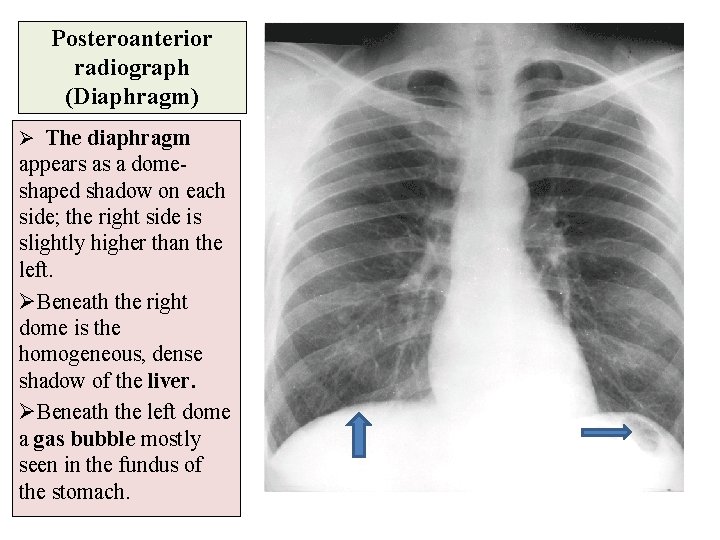

Posteroanterior radiograph (Diaphragm) Ø The diaphragm appears as a domeshaped shadow on each side; the right side is slightly higher than the left. ØBeneath the right dome is the homogeneous, dense shadow of the liver. ØBeneath the left dome a gas bubble mostly seen in the fundus of the stomach.

Posteroanterior radiograph (Diaphragm) ØNote the costo- phrenic angle, where the diaphragm meets the thoracic wall. ØThe angle becomes blunt or obscured due to minimal pleural fluid (effusion) or fibrosis. ØAlso note the cardiophrenic angle where the diaphragm meet the heart.